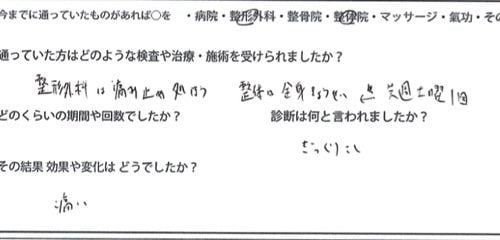

僕の整体院に来る前に整形外科や

他の整体院に行かれたようですが

特に何をする事もなく痛み止めを処方されて

勝手に治るのを待っている状態だったり

痛みのある腰を揉んでくれたり・・でしたが

痛みが引かずお困りでした。

施術前後のアンケート